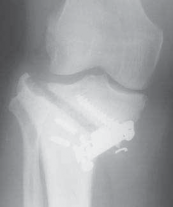

5. Radiographic evaluation in planning for an HTO is of paramount importance. Routine radiographs to obtain include bilateral anteroposterior (AP) standing, bilateral posteroanterior (PA) 45-degree flexed (ie, skier’s view), lateral view of affected knee, and bilateral Merchant views.

1. The AP standing and PA 45-degree flexed views allow the determination and initial grading of medial or lateral joint space narrowing. Joint space narrowing often can be found at the posterior condylar area and, therefore, may be missed on a routine AP standing knee radiograph.

1. Flexing the knee to 45 degrees allows a different area of the femoral condyle to be evaluated tangentially by the xray beam and may reveal significant arthritic change (

FIG 2A,B

).

FIG 2 • A. AP radiograph of the right knee showing significant narrowing of the medial joint space with flattening of the medial femoral condyle and osteo-phyte formation. B. PA 45-degree flexed view (ie, Rosenberg view) of the same knee is obtained to show a different tangential view of the condyles. In this view, the patient has cartilage space remaining, but the medial compartment is narrowed. The numbers written in the condyles represent millimeters of joint space. C. Mechanical axis view of the bilateral lower extremities shows severe bilateral varus deformities of the lower extremity. Although the picture is underpenetrated toward the femoral heads, the steps for obtaining the mechanical axis are as follows: (1) Mark the center of the femoral head. (2) Mark the center of the ankle. (3) Draw a straight line between them (ie, the most medial line on the illustration). If the line is medial to the center of

the knee, then the patient is in varus. If it is lateral,

the patient is in valgus. In this case, the patient is in severe varus.